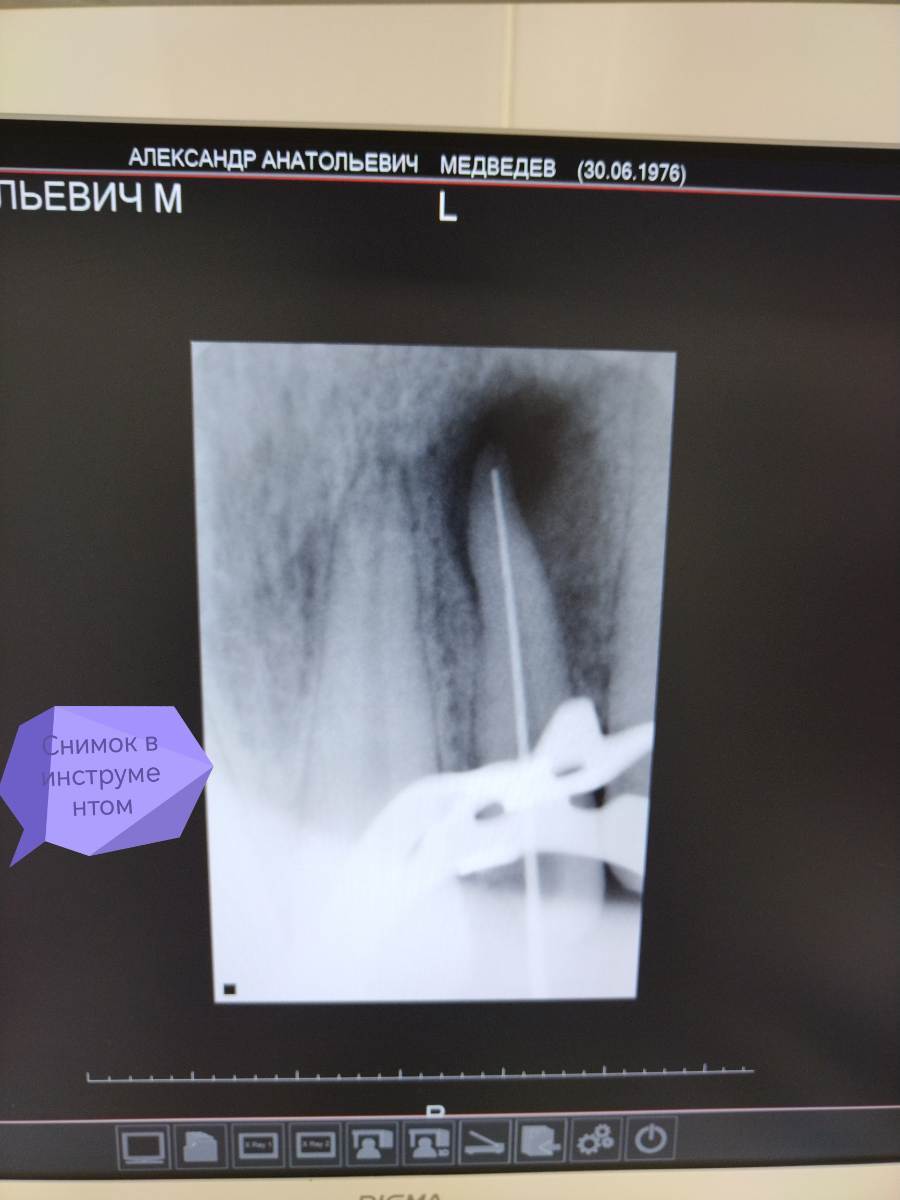

АВА2018 Опубликовано 28 декабря, 2025 Поделиться Опубликовано 28 декабря, 2025 Цитата Добрый вечер, коллеги 🙂Оцените, пожалуйста, качество пломбирования зуба 22 и есть ли перерасширение устьевой части канала.... Протокол работы: В 1 посещение-Механическая и медикаментозная обработка канала ручными к-файлами до 45 размера , промывание 3% раствором паркана, ЭДТА, активация эндоактиватором, вода. Изначальный размер канала 25 размер к -файла....Высушивание, получен экссудат в небольшом количестве. Временная пломбировка кальсептом на 2 недели. 2 посещение-Жалоб нет. Снятие пломбы, вымывание кальция из канала 3 % раствором паркана, водой дистиллированной. Долго не могла вымыть кальций из канала, при активации эндоактиватором выходили стружки кальция.... Постоянная пломбирование пастой Н+ с гуттаперчевыми штифтами методом латеральной конденсации. Пациенту придёт через 6 месяцев для контроля заживления.. Ссылка на комментарий

АВА2018 Опубликовано 28 декабря, 2025 Автор Поделиться Опубликовано 28 декабря, 2025 Скажите, пожалуйста, есть ли перерасширение цервикального дентина? Я работала без устьевика... Но на снимке отчётливо вижу перерасширение... Да и вообще проблема у меня с вымыванием кальция из каналов , я не могу понять, вымыла ли я его полностью, всё равно идёт белая стружка при активации. Я потом беру мастер-файл и н-файл по стенкам вожу и всё равно идёт белая стружка... Есть вообще ощущение, что я каналы перерасширяю.... Фанатизм мой до добра не доведёт... 😩Переживаю ща пациента.... Ну вот это перерасширение или просто ракурс такой? Ссылка на комментарий

Carioznik Опубликовано 30 декабря, 2025 Поделиться Опубликовано 30 декабря, 2025 В 29.12.2025 в 00:11, АВА2018 сказал: обработка канала ручными к-файлами до 45 В 29.12.2025 в 00:15, АВА2018 сказал: работала без устьевика Еще забы написать: При такой инструментальной обработке - не должно быть перересширения. Если только H-файлом "наскребли" (но это уж надо сильно постараться). Скорее всего анатомия изначально такая+ ракурс еще возможно.... По кальцию - да, вымывать его не просто, но УЗ - хорошо справляется с этим. Просто эндоактиватором, да,. плохо отмывается и долго Ps: с Наступающим! 1 Ссылка на комментарий